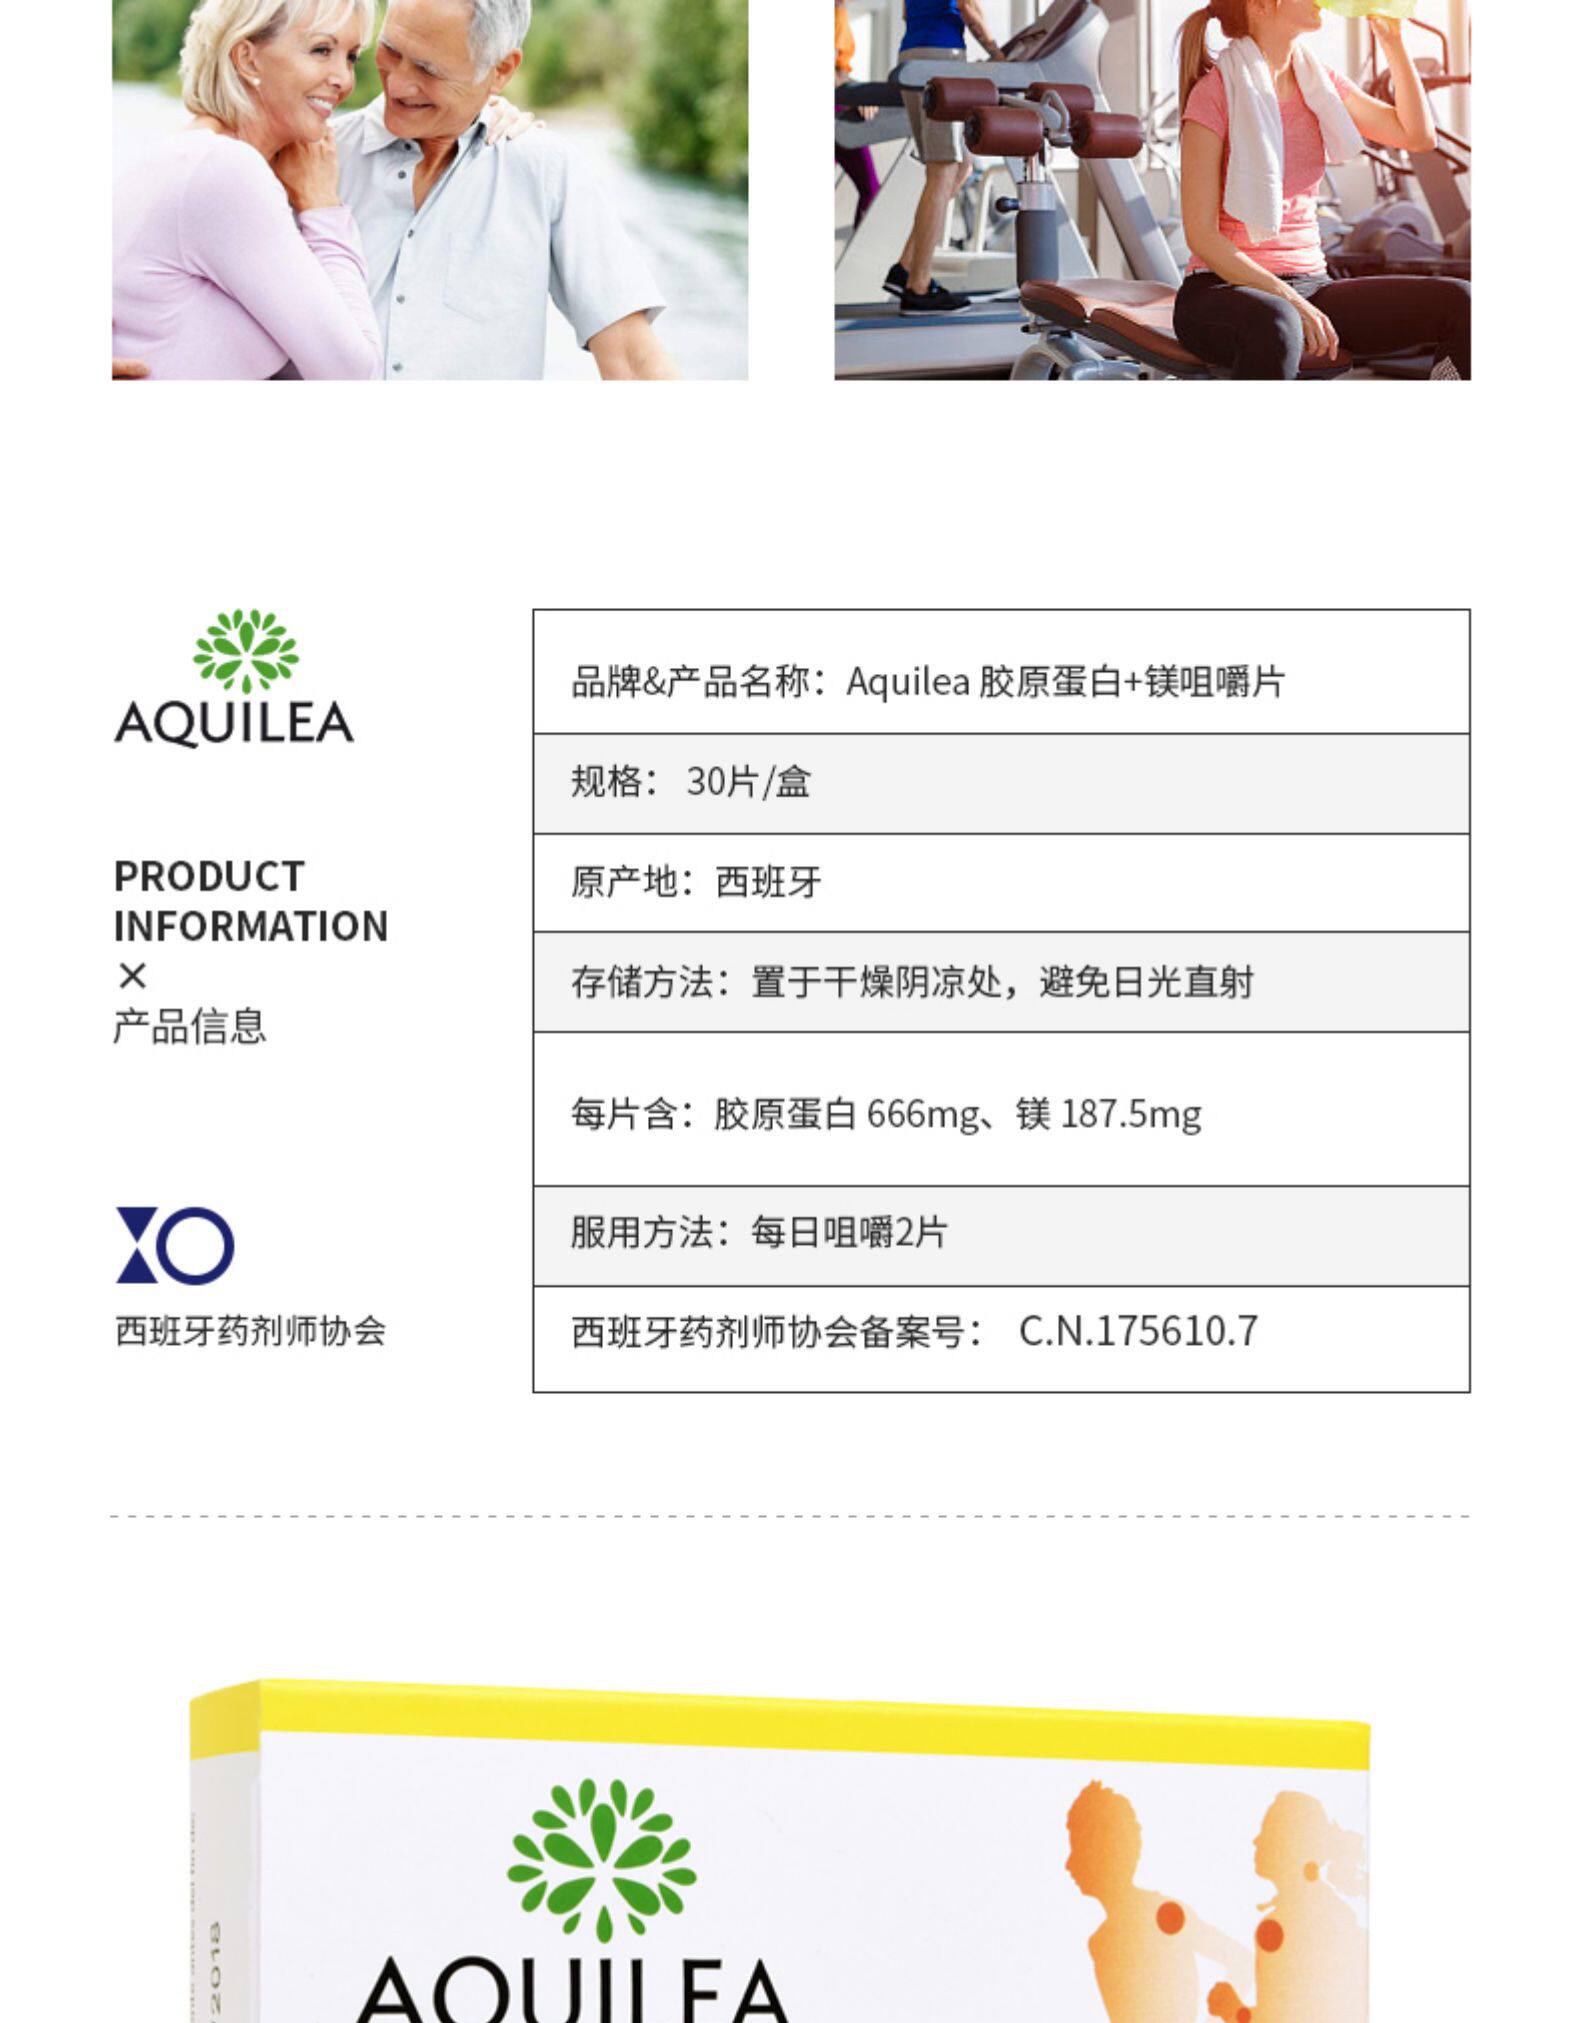

AQUILEA Коллаген, Испания, для среднего возраста

Описание товараPGRpdiBzdHlsZT0id2lkdGg6IDc5MC4wcHg7aGVpZ2h0OiAxNDU2My4wcHg7b3ZlcmZsb3c6IGhpZGRlbjsiPjxkaXYgc3R5bGU9IndpZHRoOiA3OTAuMHB4O2hlaWdodDogMTQ1NjMuMHB4O292ZXJmbG93OiBoaWRkZW47Ij48aW1nIHN0eWxlPSJkaXNwbGF5OiBibG9jazt3aWR0aDogMTAwLjAlOyIgc3JjPSJodHRwczovL2ltZy5hbGljZG4uY29tL2ltZ2V4dHJhL2kzLzMzODU3MDE4MzIvTzFDTjAxYkxpQkZOMVBQNkJhVTN0akFfISEzMzg1NzAxODMyLmpwZyI+PGltZyBzdHlsZT0iZGlzcGxheTogYmxvY2s7d2lkdGg6IDEwMC4wJTsiIHNyYz0iaHR0cHM6Ly9pbWcuYWxpY2RuLmNvbS9pbWdleHRyYS9pNC8zMzg1NzAxODMyL08xQ04wMU0wNDloYjFQUDZCYklVNU55XyEhMzM4NTcwMTgzMi5qcGciPjxpbWcgc3R5bGU9ImRpc3BsYXk6IGJsb2NrO3dpZHRoOiAxMDAuMCU7IiBzcmM9Imh0dHBzOi8vaW1nLmFsaWNkbi5jb20vaW1nZXh0cmEvaTQvMzM4NTcwMTgzMi9PMUNOMDE1OHpnN0oxUFA2QmNJTEREUF8hITMzODU3MDE4MzIuanBnIj48aW1nIHN0eWxlPSJkaXNwbGF5OiBibG9jazt3aWR0aDogMTAwLjAlOyIgc3JjPSJodHRwczovL2ltZy5hbGljZG4uY29tL2ltZ2V4dHJhL2kyLzMzODU3MDE4MzIvTzFDTjAxUmo5cFVQMVBQNkFyM2NTN3hfISEzMzg1NzAxODMyLmpwZyI+PGltZyBzdHlsZT0iZGlzcGxheTogYmxvY2s7d2lkdGg6IDEwMC4wJTsiIHNyYz0iaHR0cHM6Ly9pbWcuYWxpY2RuLmNvbS9pbWdleHRyYS9pNC8zMzg1NzAxODMyL08xQ04wMXRhN0kzWTFQUDZCZVlITDJTXyEhMzM4NTcwMTgzMi5qcGciPjxpbWcgc3R5bGU9ImRpc3BsYXk6IGJsb2NrO3dpZHRoOiAxMDAuMCU7IiBzcmM9Imh0dHBzOi8vaW1nLmFsaWNkbi5jb20vaW1nZXh0cmEvaTIvMzM4NTcwMTgzMi9PMUNOMDF5akxDdkkxUFA2QmR4YmQxVl8hITMzODU3MDE4MzIuanBnIj48aW1nIHN0eWxlPSJkaXNwbGF5OiBibG9jazt3aWR0aDogMTAwLjAlOyIgc3JjPSJodHRwczovL2ltZy5hbGljZG4uY29tL2ltZ2V4dHJhL2kxLzMzODU3MDE4MzIvTzFDTjAxWVNPYUhYMVBQNkJhVTR5RXJfISEzMzg1NzAxODMyLmpwZyI+PGltZyBzdHlsZT0iZGlzcGxheTogYmxvY2s7d2lkdGg6IDEwMC4wJTsiIHNyYz0iaHR0cHM6Ly9pbWcuYWxpY2RuLmNvbS9pbWdleHRyYS9pMy8zMzg1NzAxODMyL08xQ04wMWJUbVM4RDFQUDZCWGdTSU1TXyEhMzM4NTcwMTgzMi5qcGciPjxpbWcgc3R5bGU9ImRpc3BsYXk6IGJsb2NrO3dpZHRoOiAxMDAuMCU7IiBzcmM9Imh0dHBzOi8vaW1nLmFsaWNkbi5jb20vaW1nZXh0cmEvaTEvMzM4NTcwMTgzMi9PMUNOMDFPWHlNNEYxUFA2QmF2d1A1WV8hITMzODU3MDE4MzIuanBnIj48aW1nIHN0eWxlPSJkaXNwbGF5OiBibG9jazt3aWR0aDogMTAwLjAlOyIgc3JjPSJodHRwczovL2ltZy5hbGljZG4uY29tL2ltZ2V4dHJhL2k0LzMzODU3MDE4MzIvTzFDTjAxUThxWWVmMVBQNkJmRmp5d3dfISEzMzg1NzAxODMyLmpwZyI+PGltZyBzdHlsZT0iZGlzcGxheTogYmxvY2s7d2lkdGg6IDEwMC4wJTsiIHNyYz0iaHR0cHM6Ly9pbWcuYWxpY2RuLmNvbS9pbWdleHRyYS9pMi8zMzg1NzAxODMyL1RCMnRIV3hvMGZKOEtKankwRmVYWFhLRVhYYV8hITMzODU3MDE4MzIuanBnIj48aW1nIHN0eWxlPSJkaXNwbGF5OiBibG9jazt3aWR0aDogMTAwLjAlOyIgc3JjPSJodHRwczovL2ltZy5hbGljZG4uY29tL2ltZ2V4dHJhL2kzLzMzODU3MDE4MzIvTzFDTjAxUWRRRzFIMVBQNkJlWUZheWpfISEzMzg1NzAxODMyLmpwZyI+PGltZyBzdHlsZT0iZGlzcGxheTogYmxvY2s7d2lkdGg6IDEwMC4wJTsiIHNyYz0iaHR0cHM6Ly9pbWcuYWxpY2RuLmNvbS9pbWdleHRyYS9pNC8zMzg1NzAxODMyL08xQ04wMWJ4WVBBYzFQUDZCZDlvRlBxXyEhMzM4NTcwMTgzMi5qcGciPjxpbWcgc3R5bGU9ImRpc3BsYXk6IGJsb2NrO3dpZHRoOiAxMDAuMCU7IiBzcmM9Imh0dHBzOi8vaW1nLmFsaWNkbi5jb20vaW1nZXh0cmEvaTQvMzM4NTcwMTgzMi9UQjJBRUtEbzIySDhLSmp5MEZjWFhhRGxGWGFfISEzMzg1NzAxODMyLmpwZyI+PGltZyBzdHlsZT0iZGlzcGxheTogYmxvY2s7d2lkdGg6IDEwMC4wJTsiIHNyYz0iaHR0cHM6Ly9pbWcuYWxpY2RuLmNvbS9pbWdleHRyYS9pMi8zMzg1NzAxODMyL08xQ04wMU80RDJrRTFQUDZCYklUVTB5XyEhMzM4NTcwMTgzMi5qcGciPjxpbWcgc3R5bGU9ImRpc3BsYXk6IGJsb2NrO3dpZHRoOiAxMDAuMCU7IiBzcmM9Imh0dHBzOi8vaW1nLmFsaWNkbi5jb20vaW1nZXh0cmEvaTMvMzM4NTcwMTgzMi9PMUNOMDFPUW9CcFExUFA2QlN5SXB0SV8hITMzODU3MDE4MzIuanBnIj48aW1nIHN0eWxlPSJkaXNwbGF5OiBibG9jazt3aWR0aDogMTAwLjAlOyIgc3JjPSJodHRwczovL2ltZy5hbGljZG4uY29tL2ltZ2V4dHJhL2kxLzMzODU3MDE4MzIvVEIyWXBuM29ZWUk4S0pqeTBGYVhYYkFpVlhhXyEhMzM4NTcwMTgzMi5qcGciPjxpbWcgc3R5bGU9ImRpc3BsYXk6IGJsb2NrO3dpZHRoOiAxMDAuMCU7IiBzcmM9Imh0dHBzOi8vaW1nLmFsaWNkbi5jb20vaW1nZXh0cmEvaTMvMzM4NTcwMTgzMi9PMUNOMDFWaDV0VHQxUFA2QmFVM3BiZl8hITMzODU3MDE4MzIuanBnIj48aW1nIHN0eWxlPSJkaXNwbGF5OiBibG9jazt3aWR0aDogMTAwLjAlOyIgc3JjPSJodHRwczovL2ltZy5hbGljZG4uY29tL2ltZ2V4dHJhL2kxLzMzODU3MDE4MzIvTzFDTjAxQmpNMzg2MVBQNkJlWUhMM2lfISEzMzg1NzAxODMyLmpwZyI+PGltZyBzdHlsZT0iZGlzcGxheTogYmxvY2s7d2lkdGg6IDEwMC4wJTsiIHNyYz0iaHR0cHM6Ly9pbWcuYWxpY2RuLmNvbS9pbWdleHRyYS9pMy8zMzg1NzAxODMyL08xQ04wMURxeUJlUDFQUDZCYklVOWFFXyEhMzM4NTcwMTgzMi5qcGciPjxpbWcgc3R5bGU9ImRpc3BsYXk6IGJsb2NrO3dpZHRoOiAxMDAuMCU7IiBzcmM9Imh0dHBzOi8vaW1nLmFsaWNkbi5jb20vaW1nZXh0cmEvaTIvMzM4NTcwMTgzMi9PMUNOMDE0YXMyenQxUFA2QlN5S1JlbF8hITMzODU3MDE4MzIuanBnIj48L2Rpdj48L2Rpdj4=